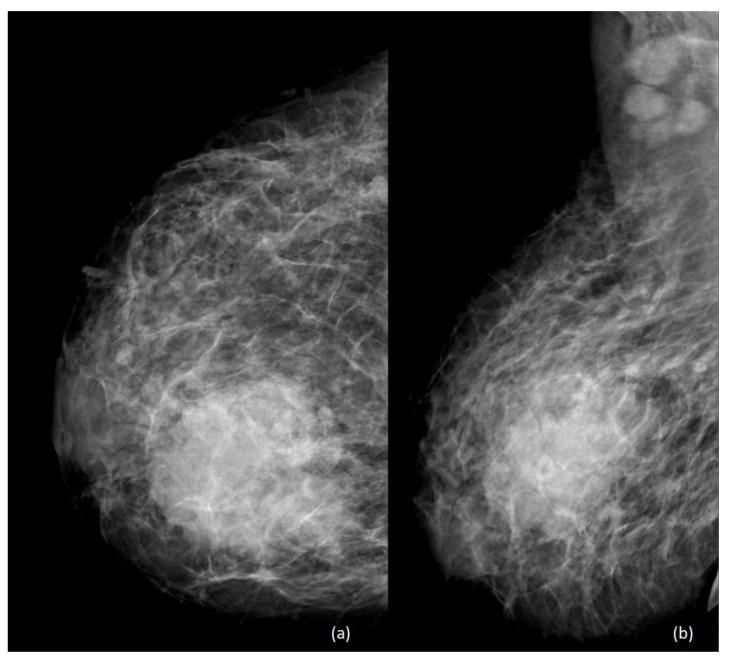

Pregnancy-associated breast cancer (PABC) is commonly defined as a breast cancer occurring during pregnancy, throughout 1 year postpartum, or during lactation. Despite being a rare circumstance, PABC is one of the most common types of malignancies occurring during pregnancy and lactation, with growing incidence in developed countries, due both to decreasing age at onset of breast cancer and to increasing maternal age. Diagnosis and management of malignancy in the prenatal and postnatal settings are challenging for practitioners, as the structural and functional changes that the breast undergoes may be misleading for both the radiologist and the clinician. Furthermore, safety concerns for the mother and child, as well as psychological aspects in this unique and delicate condition, need to be constantly considered. In this comprehensive review, clinical, diagnostic, and therapeutic aspects of PABC (including surgery, chemotherapy and other systemic treatments, and radiotherapy) are presented and fully discussed, based on medical literature, current international clinical guidelines, and systematic practice.

妊娠相关乳腺癌(PABC)通常定义为在妊娠期、产后1年内或哺乳期发生的乳腺癌。尽管这种情况较为罕见,但PABC是妊娠和哺乳期最常见的恶性肿瘤类型之一,在发达国家其发病率呈上升趋势,这是由于乳腺癌发病年龄降低以及产妇年龄增加所致。对于从业者而言,产前和产后环境中恶性肿瘤的诊断和管理具有挑战性,因为乳房所经历的结构和功能变化可能会对放射科医生和临床医生产生误导。此外,需要持续考虑母婴的安全问题以及这种独特且微妙情况下的心理因素。在这篇全面综述中,基于医学文献、当前国际临床指南和系统实践,阐述并充分讨论了PABC的临床、诊断和治疗方面(包括手术、化疗和其他全身治疗以及放疗)。